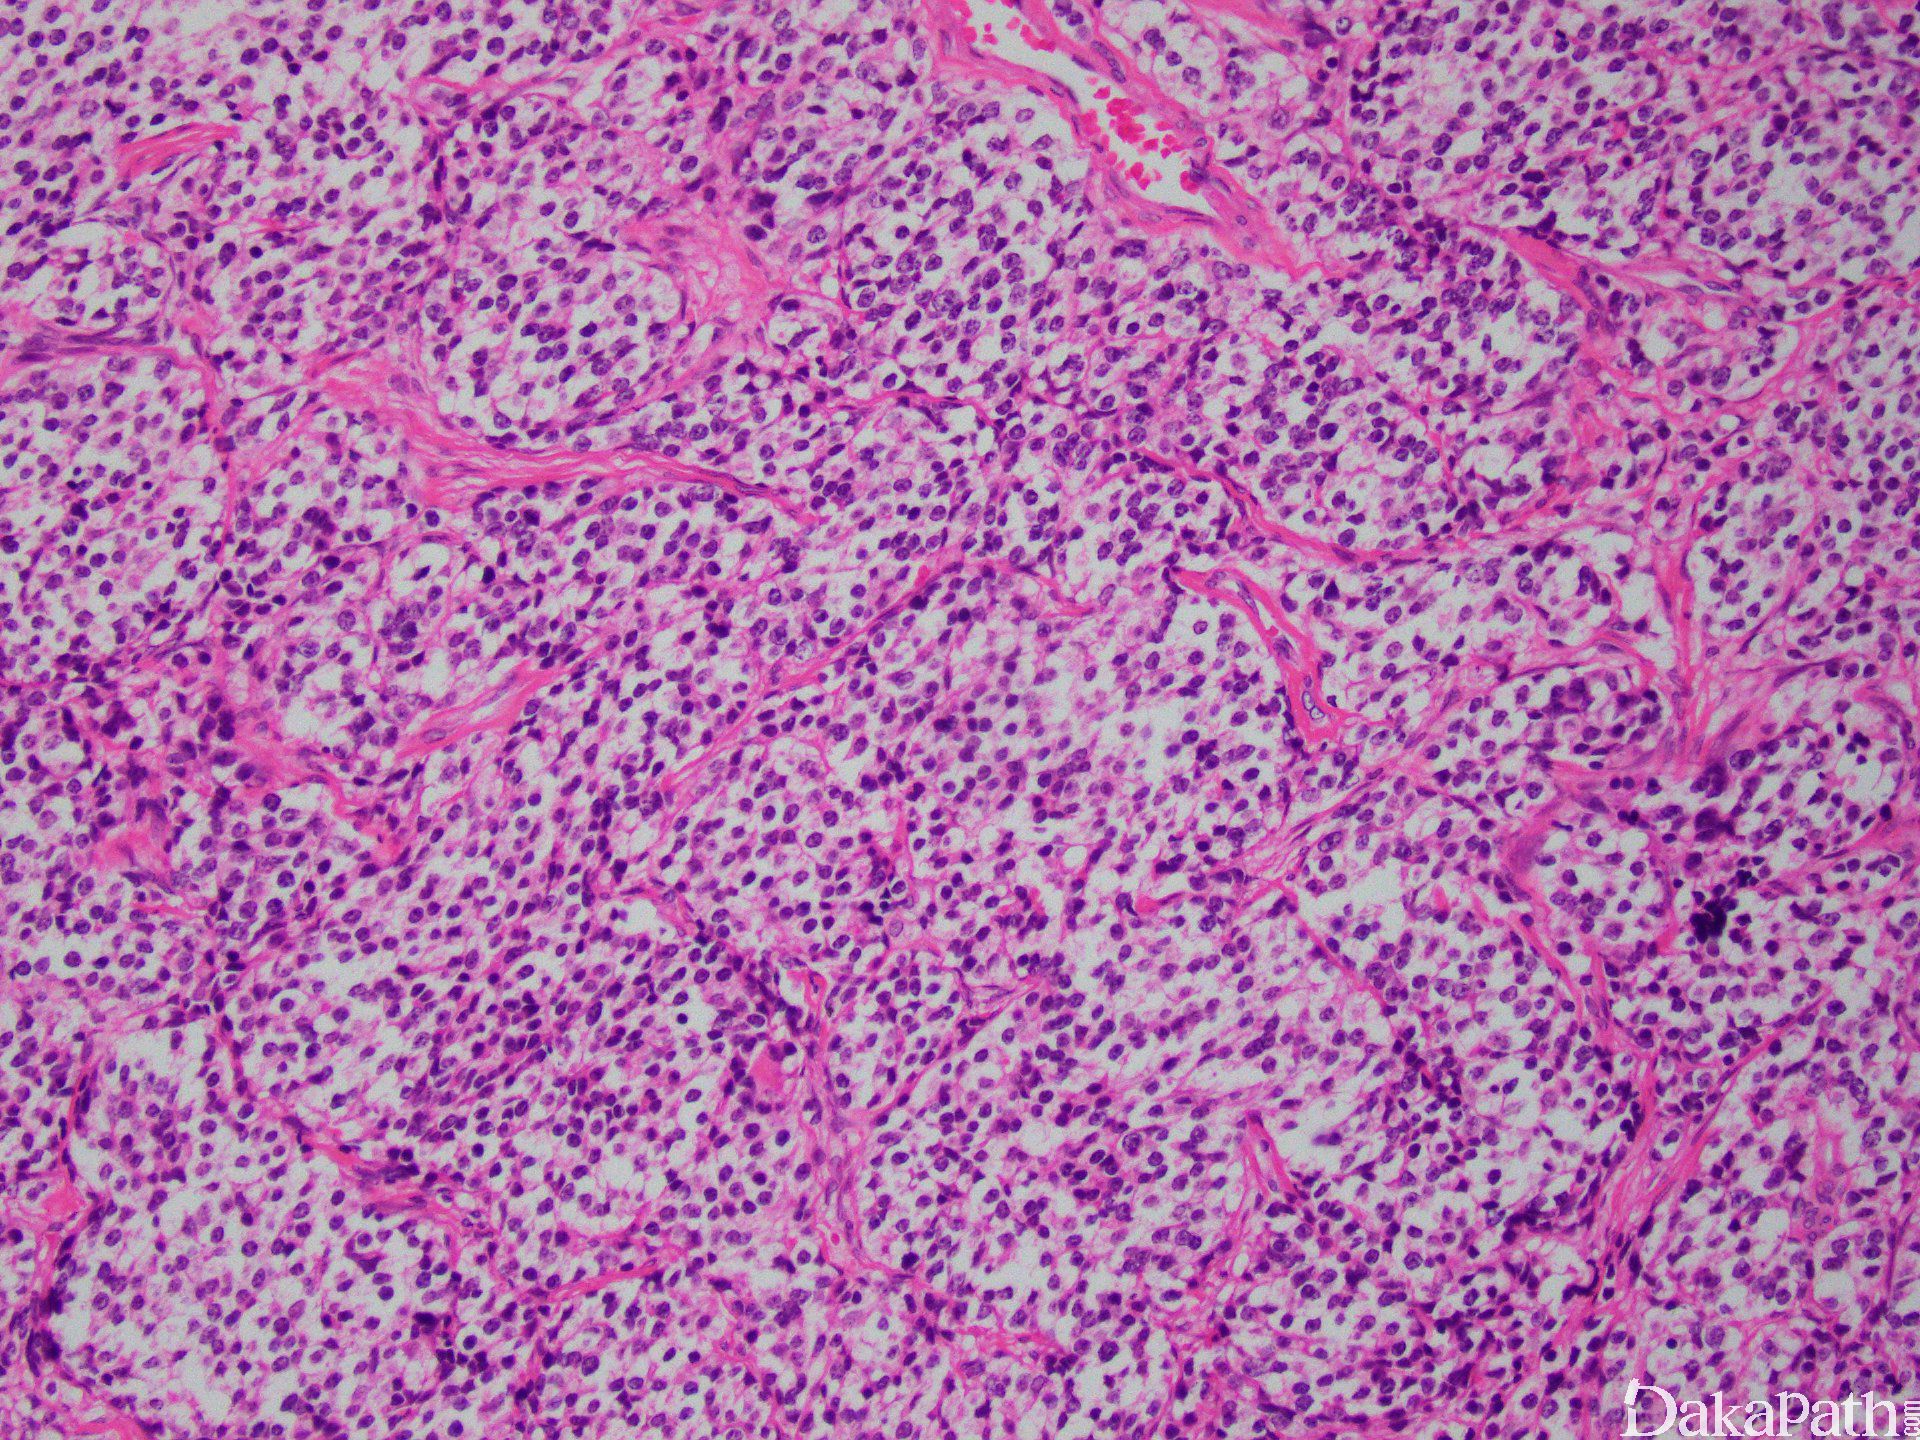

组织学改变基于分化成程度不同而呈不同,原始神经母细胞分叶状排列(不管分级如何)。叶状结构之间富于纤维血管间隔,支持细胞常位于细胞巢周边。

肿瘤细胞呈经典小圆蓝细胞,比成熟淋巴细胞稍微大一些,核浆比高,小而一致的胞核伴细致、椒盐样染色质分布,胞核比较小或缺席。细胞呈合胞体样。可见中央为神经丝状物构成的菊形团(Homer Wright)。

可见两种菊形团形式:假菊形团 (Homer Wright)及真菊形团(Flexner-Wintersteiner)。假菊形团见于 30%的病例,肿瘤细胞栅栏状、套样围绕在神经丝样、水肿样神经基质的周围,可见于 1 级或 2 级。真菊形团见于 5%的病例,中空导管样伴非纤毛样柱状细胞,可见与 3 级或 4 级。围血管性菊形团没有诊断价值。